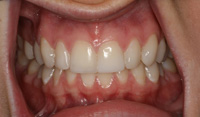

Lingual Veneers - Why? To restore worn-away enamel from acid erosion due to eating disorders.Lingual veneers are veneers that are placed on the inside, or lingual, surface of the front teeth. Rather than remove any healthy enamel from the remaining front and back sides of the teeth to do crowns, lingual veneers offer a conservative alternative for those who have experienced acid erosion, or tooth wear, of the lingual surfaces due to the detrimental effects of eating disorders such as bulimia. The goal is to build up and restore worn away teeth while preserving as much of the natural, beautiful and healthy tooth structure as possible. This strengthens and reinforces the tooth from further damage and drastically reduces sensitivity so a healthy diet and lifestyle can be resumed. Professional dental help for bulimia It is important to seek dental care if you have bulimia and to openly share with the dentist what is happening. Many dentists are caring professional people who understand the problems with bulimia and want to help. Without the dentist's help, the dental consequences of your bulimia can be severe. Dr. Berland can usually provide all of the dental services needed to restore the bulimic patient back to good dental health in a confidential and private manner. Additionally, Dr. Berland can help a bulimic patient manage the condition so that, even if they are continuing to have problems, the dental consequences of bulimia are lessened or eliminated. The Dallas Dental Arts services can be specially arranged for a bulimic patient so that all needed dental treatment can be intensively completed in a short period of time. This makes it possible for patients from out of town to complete their desperately needed dental care confidentially and in as few visits as possible. The Dallas Dental Arts can also assist in obtaining the funds for this care so everything that needs to be done can be completed. For more information on financial assistance, please click here. Dr. Berland has successfully cared for many patients suffering from bulimia and would be pleased to meet with you in a confidential consultation. Here, You can privately discuss your choices in dealing with your bulimia. Dr. Berland understands that you are struggling with bulimia and that it may take time to deal with the consequences of your bulimia. Privately speaking with Dr. Berland can be your first step in conquering your bulimia. Please consider calling (214)999-0110 and scheduling a consultation. You do not have to say why you are visiting, just that you would like a private consultation. If calling for an appointment is too embarrassing, you can first email Dr. Berland at drberland@dallasdentalspa.com or you can schedule a consultation and privately email him to let Dr. Berland know that you wish to talk about your bulimia. This young lady came to our office looking for a way to improve her smile, self-image and most importantly, her health. As a recovering bulimic patient, she had endured years of damage to her enamel from her previous history of eating disorders. In her case, the erosion wore all the way through her enamel and even into the soft, sensitive inner tooth layer, the dentin. She sought us out to find a way to restore her smile without further compromising the fragile condition of her teeth. Other dentists discussed filing her already thinned down teeth further and "strengthening" them with porcelain crowns. Our approach was completely different. Why take away more when you don’t have much to begin with? We recommended she try lingual resin veneers (on the backside of her teeth) followed by cosmetic one-stop bonding on the front and especially the edges of her teeth. This is a completely noninvasive and a purely additive procedure. She would be adding strength to her teeth, fortifying them rather than removing any of her remaining enamel, thereby reinforcing her teeth, improving her dental condition and creating the beautiful, yet natural, smile she desired. When the patient heard of this conservative treatment alternative, it made sense to her to preserve her teeth to maintain her health and restore her smile. Not only were the back sides of her teeth built out, length was added to replace what was worn over the years for a more youthful smile. After the no-shots, no-drilling, and no-pain appointment, her teeth were no longer sensitive to sweets, hot or cold. The patient was very pleased with her results. She not only gained a beautiful, new smile, but she also had a renewed confidence in herself and a reassurance of a healthier smile – and that means a healthier lifestyle as well! With all the focus of the media on diets, exercise equipment and personal care products, people are more concerned with their appearance and physical health than ever. In an effort to meet today's standard of beauty and "health", many people are quick to try the newest crash diet fad without ever realizing that this may, in fact, be the incorrect way to diet. These crash dieters who excessively fast, or try every new trend, tend to have a lack of, or decrease in certain vitamins, most notably Vitamins D, B-12 and calcium. They also tend to lack certain minerals and proteins in their diets. These are very important vitamins especially for the health of the teeth and gums. What can occur is that dieters tend to have a diet high in fruits which may contain a high content of natural sugars. These sugars tend to decay and erode the enamel of the teeth. Mints, used to combat the bad breath associated from Ketosis caused by an unbalanced protein diet and "so-called" Power Bars can further decay the teeth. Dieters also tend to take diet pills that may cause a decrease in saliva flow as a side effect. This decrease in saliva flow tends to increase the acid levels in the mouth which may cause an increased level of cavity formation. Antidepressants and decongestants have the same effect. Dr. Berland cares about the health and well-being of his patients. If you are currently on a diet that restricts certain food groups and/or you are taking a supplement or prescription diet aid, your oral health may compromised and in need of attention. Click here to see an example of the effects of eating disorders on your teeth. Please discuss with Dr. Berland at your next appointment any of these changes in diet or methods of weight control and any problems or discomfort you may be experiencing in your teeth and gums. Dr. Berland has many conservative measures to prevent and alleviate these conditions. Preventing a dental situation before it becomes a problem can save not only your teeth-- but, discomfort, time, money and your health. |